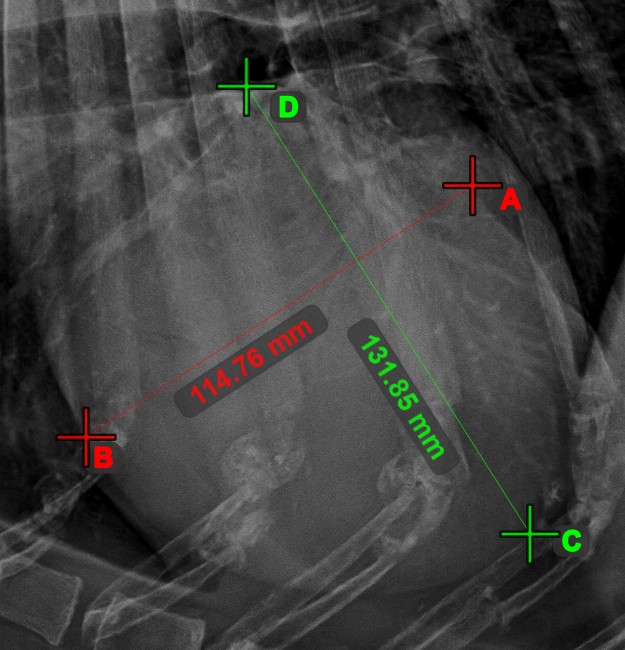

Line Measurement¶

Select the Line Measurement tool and assign it to one of the available mouse buttons. Place the start and end points on the scene or select them from already existing points on the image. The distance between the two points will be automatically

calculated by using the default calibration data, or the recalibrated data by the length calibration measurement.

Modify the start and end point by using the Select/Move Item tool. The distance between the two points will be automatically recalculated.